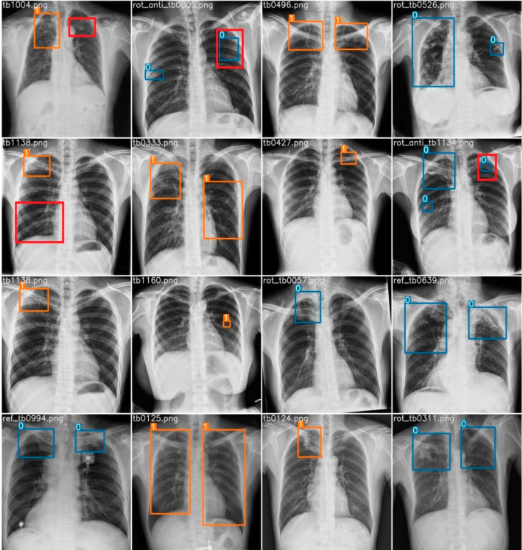

AyurEye – Tuberculosis Diagnosis System

It is a comprehensive tuberculosis diagnosis system that provides an efficient diagnosis of tuberculosis by analyzing X-ray images of the lungs, created using Django, Flutter, and ML/AI.

Contributed to website development and both frontend and backend functionalities and features enabling the identification and visualization of potential tuberculosis-affected areas through the drawing of bounding boxes.